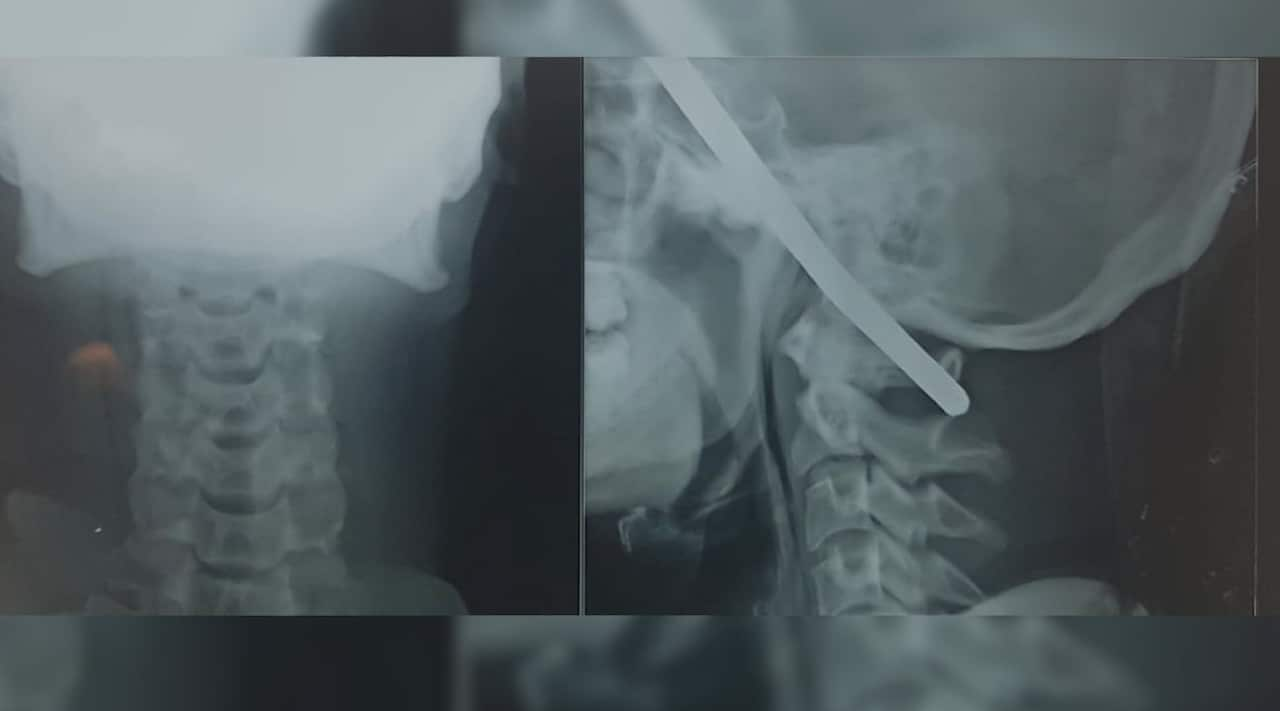

Sanjay Bahe from Balaghat, India was repairing a well at a construction site in Madhya Pradesh when he reportedly fell and an iron rod pierced his skull.

A team of six doctors removed the rod, which luckily didn't hit any major blood vessels in the brain.